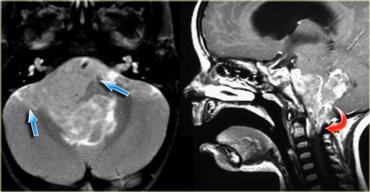

U màng nội tủy (Ependymoma) lan rộng đến vùng trước cầu não (mũi tên xanh lam) và vào lỗ chẩm (mũi tên đỏ).

U màng nội tủy (ependymoma) của não thất IV ở trẻ em có xu hướng lan rộng qua lỗ Magendie đến bể lớn (cisterna magna) và qua các lỗ bên Luschka đến góc cầu tiểu não (hình minh họa).